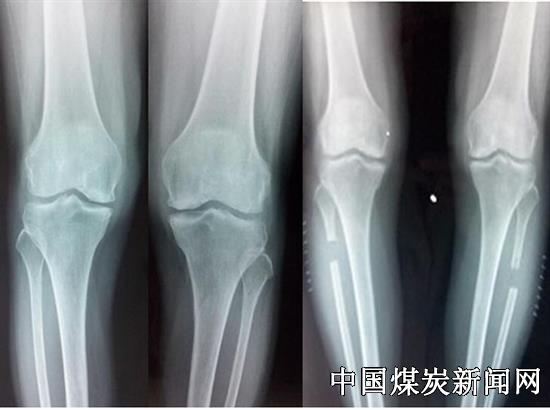

冀中能源峰峰集团总医院腓骨近端段切术治疗严重膝关节炎

膝关节骨性关节炎是中老年人的常见病,近两年来,冀中能源峰峰集团总医院骨一科依据河北医科大学第三医院张英泽教授根据膝关节两侧不均匀沉降理论设计的“腓骨近端段切术”治疗膝关节骨性关节炎,为许多患者解决了关节疼痛不能行走、难以下蹲的情况,治疗效果显著。

一名76岁女性患者,双腿膝关节疼痛不能下蹲,行走跛行10余年,经口服药物,贴膏药,小针刀,理疗,封闭等多种保守治疗没有效果,来峰峰集团总医院骨一科就诊,被诊断双膝关节骨性关节炎。患者还患有高血压、糖尿病、脑梗塞等多种内科疾病。经骨一科主任马同敏、大夫杨辉等为其行双侧腓骨近端段切术,患者由术前双膝关节最大下蹲角度约45度,WOMAC评分39分,等级差的情况经手术治疗后最大下蹲角度达到约120度,WOMAC评分9分,等级优。1年后回访患者其膝关节功能恢复良好。另一名65岁双膝关节骨性关节炎患者,疼痛跛行30余年,经过多种保守治疗,依旧效果不佳,行走困难,在峰峰集团总医院骨一科施行双侧腓骨近端段切手术,恢复行走自如。目前他们已经顺利开展几十例此类手术,效果得到了患者和医师的认可。这一手术为广大患有膝关节骨性关节炎的患者提供了一个新的治疗方法,手术拥有微创、并发症少等优势,适用于所有膝关节骨性关节炎保守治疗无效患者,尤其适用于身体条件差、不能行膝关节置换的患者。